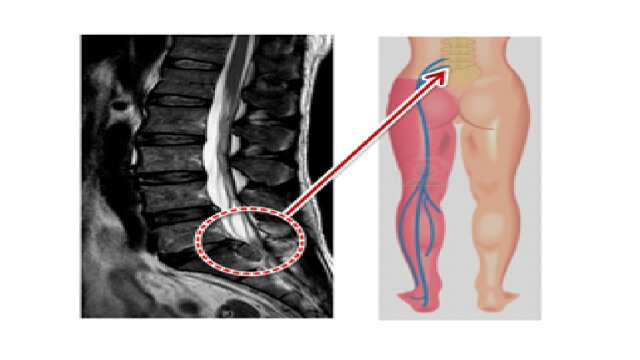

추간판 탈출증이라 불리는 허리디스크 증상은 크게 3단계로 나눌 수 있어요. 1단계는 내부 섬유륜이 파열하여 수핵이 빵빵한 상태, 2단계는 섬유륜 전체가 파열되어 수핵이 탈출하는 단계, 3단계는 완전히 탈출해 버린 단계입니다.

단계마다 느끼는 증상들이 조금씩 다른데요. 디스크의 보호막이 약간 찢어졌고 디스크가 약간 튀어 주변의 신경 뿌리에 닿으면 염증성의 통증이 발생하기 시작하면서 점점 증상이 심해지면 디스크의 파열은 골수를 이루고 있는 핵이 튀어나오면서 신경에 대한 물리적 압박을 가하고 참을 수 없는 아픔을 유발하게 돼요.